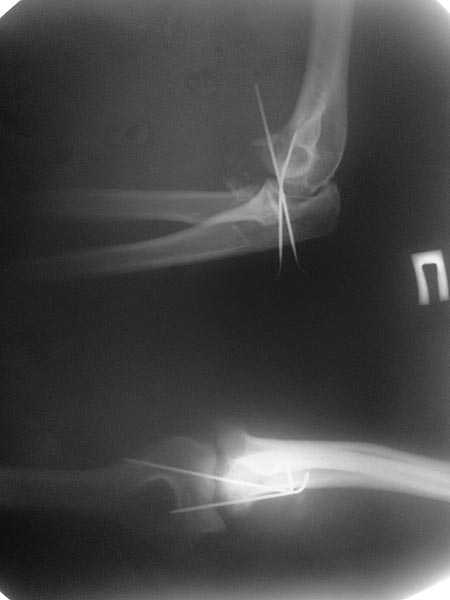

В общем, я хотел сообщить об алгоритме, который применяем у себя. Еще в 1998 году мой партнер по работе Kathy Kramer (скоропостижно скончалась, в ОТА под ее именем имеется грант) написала про наш опыт лечения трансартикулярной фиксацией в 29 случаев вывиха. Кстати, вспомнил прошлогодний спор коллег на Форуме, где площадь повреждения хряща спицами измеряли в мм2. Конечно, такая защита хряща радует, но при игнорированных неделями вывихах? Из-за критики повреждения хряща не позволили опубликовать статью.

Несмотря на отрицательный отзыв, некоторые нестабильные вывихи лечим трансартикулярным методом. Тонкие спицы ломаются и имеют риск внутрисуставной инфекции. Винты 3.5 мм не выдерживают, а более толстые каннюлированные винты неплохо проявили себя. Неосторожность при установке приводила к поломке тонких guide wire внутри сустава. Лучшие кортикальные в 4.5 мм и гипс на три недели. Винт удаляется, затем разработка сустава.

Иногда гипс не гарантировал стабильность и винт внутри гипса ломался. Удаление сломанного винта облегчаем, оставляя на пару мм длиннее с наружной стороны, Т.е винт через олекранон над наружный мыщелок, и никогда в трубку диафиза! Из малого разреза кончик сломанного винта удаляется без проблем.

Для примера здесь случай начатый в другом центре, а потом переправленный к нам.

Снимки: 1-2 вывих, 4-5 вторичное смещение в гипсе, реконструкция латеральной связки и капсулы 13-14, повторный вывих после реконструкции, перевод в наш центр; 18-21 временная фиксация, 22-25 трансартикулярная фиксация и нестабильная головка фиксирована спицами, 29-30 амбулаторно, 32-33 после удаления винта и спиц...